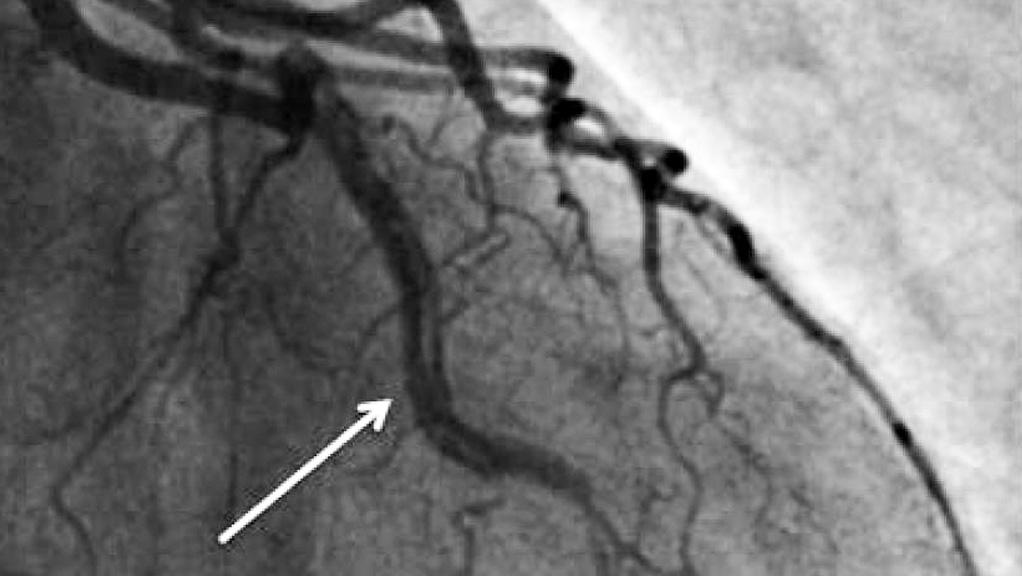

Recentemente, descobertas surpreendentes na área da cardiologia estão lançando luz sobre um problema que antes era considerado raro: a Dissecção de Artéria Coronária Espontânea (em inglês, Spontaneous…